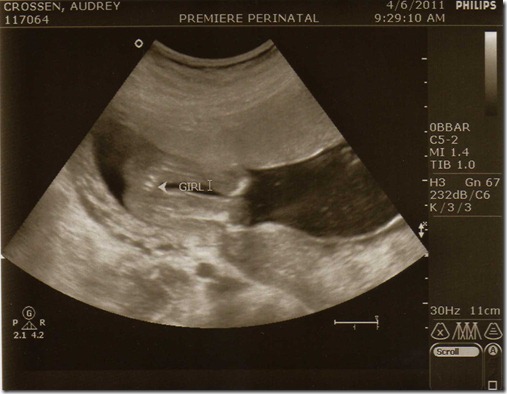

(Below) Just so there’s no confusion the doc labeled it for you all… haha

img086

Another funny story about the above pic is that the sonographer kept commenting on what a cute bum the baby had and so naturally I said “I guess it’s genetic.” Winking smile She laughed so hard she had to stop the ultrasound for a second. haha